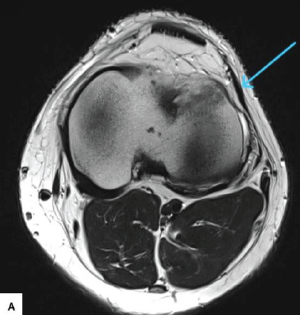

Simultaneous Anterior Cruciate Ligament Avulsion Fracture with Bilateral Posterior Meniscal Root Tears of the Knee: A Case Report

Deem Alsedais , Bader Majed Aljadaan , Hamad H Aldakhil Allah , Abdullah Adel Al-Nasser , Ibrahim Ababtain ………………………………p.222-226